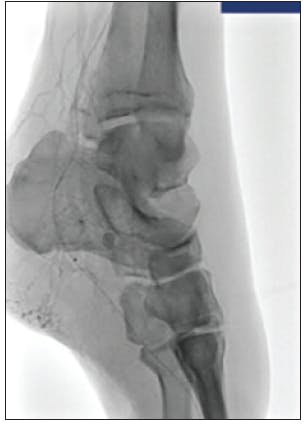

We started with laser atherectomy followed by percutaneous transluminal angioplasty of the tibial peroneal trunk, peroneal artery, and posterior tibial artery. Angiography of the posterior tibial artery revealed embolization to the heel resulting in no flow to the foot (Figure 1). After one pass with mechanical thrombectomy using CAT RX, the thrombus was removed and flow was restored to the pedal arch via the plantar posterior tibial artery (Figure 2 and Figure 3).

DISCUSSION

The Indigo System CAT RX was the preferred choice for mechanical aspiration thrombectomy to remove the distal emboli below the knee in the posterior tibial artery. The large aspiration lumen and highly trackable, low-profile design coupled with the power of the Penumbra ENGINE resulted in the successful removal of the emboli in one pass. The deliverability and continuous aspiration power were essential to achieving restoration of flow supporting a positive patient outcome to help heal this case of CLI.